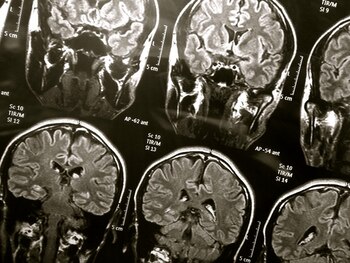

Entre algunas de las repercusiones a nivel cerebral que han sido documentadas en artículos científicos se encuentran las funciones mentales alteradas (el término médico es encefalopatía), las cuales pueden incluir problemas de atención y concentración, pérdida de memoria a corto plazo, desorientación y estupor, entre otros. En algunos casos también ha sido llamada “niebla mental” por COVID-19.

Cabe destacar que según información de científicos para el diario The New York Times, estos aún no están seguros de la causa de esta obnubilación, pues cada caso varía mucho en relación a los demás. Hasta el momento, las teorías más destacadas son que surge cuando la respuesta inmunitaria del cuerpo ante el virus no se detiene o que se debe a la inflamación de los vasos sanguíneos que van al cerebro.